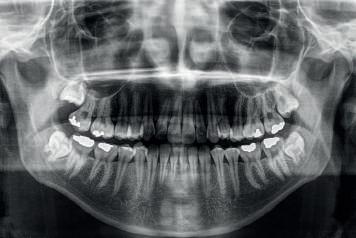

Raio X panorâmico na Odontologia

Aradiografia panorâmica é um exame de imagem que permite a análise de toda a arcada dentária, superior e inferior. São fotografias abrangentes da face e dos dentes. Portanto, oferecem uma visão que seria invisível a olho nu. Um raio x panorâmico, em geral, expõe estruturas ocultas, como dentes do siso. Revela sinais preliminares de cáries e também mostra fraturas e perda óssea. Permite que o dentista veja o que está abaixo dos dentes, cistos e focos de infecção. Ele permite que se descubra um problema que se desenvolve sem dor e sem sintomas. Os raios X panorâmicos são extra orais e simples de realizar. Geralmente envolvem o filme sendo colocado dentro da boca, mas o filme panorâmico fica oculto dentro de um mecanismo que gira em torno da parte externa da cabeça. Por meio dele também é possível observar as articulações e seios da face. Também usamos este exame para saber o posicionamento exato de todos os dentes, gengivas e mandíbula. Se você precisar de um implante dentário ou prótese dentária, ou até mesmo da documentação para aparelho ortodôntico, certamente será preciso tirar esse raio x, e aqui na Moraes Saúde você não precisa ir a outro lugar realizar este exame,

pois nossa clínica conta com este equipamento. Em todos os pacientes, antes de realizar qualquer procedimento, antes mesmo da avaliação, já é realizado este exame.

O raio X panorâmico fornece ao dentista uma visão completa de orelha a orelha, da mandíbula superior e inferior. Os objetivos mais comuns das radiografias panorâmicas são revelar o posicionamento dos dentes do siso e verificar se os implantes afetarão o nervo mandibular (o nervo que se estende em direção ao lábio inferior). E para realizar este exame, o paciente só precisa colocar o queixo no suporte do aparelho, mordendo um posicionador colocado entre os dentes com a finalidade de manter a mandíbula e a maxila ligeiramente afastadas. Depois, basta ficar parado por alguns segundos enquanto o dispositivo gira em torno do paciente, e o aparelho realiza a tomada radiográfica.

A tecnologia na Odontologia está avançando cada dia mais, em prol do bem-estar do paciente e de melhores formas de diagnóstico para os profissionais, assim como o aparelho de raio X panorâmico veio para facilitar a vida do cirurgião dentista, permitindo uma visão mais ampla do paciente, o que possibilita diagnósticos mais precisos.